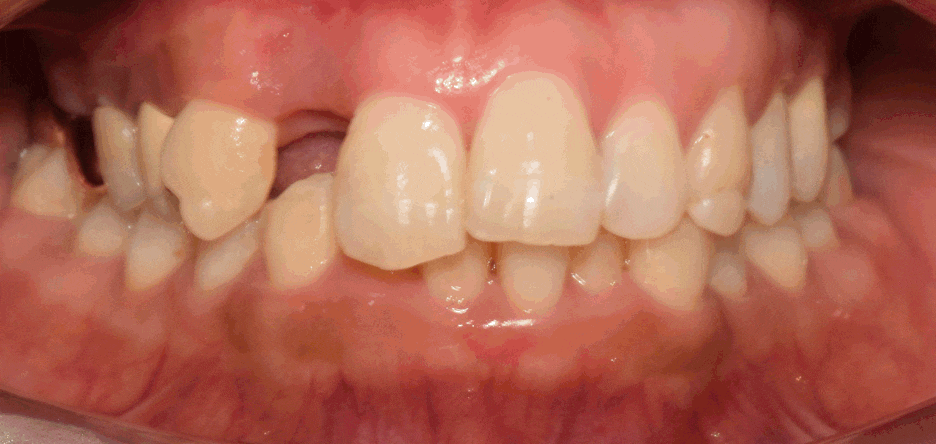

- 초진 사진

1. 치관 파절, 뿌리 끝 염증(Apical lesion) 발견

- 치아의 총생 및 과개교합 이 원인